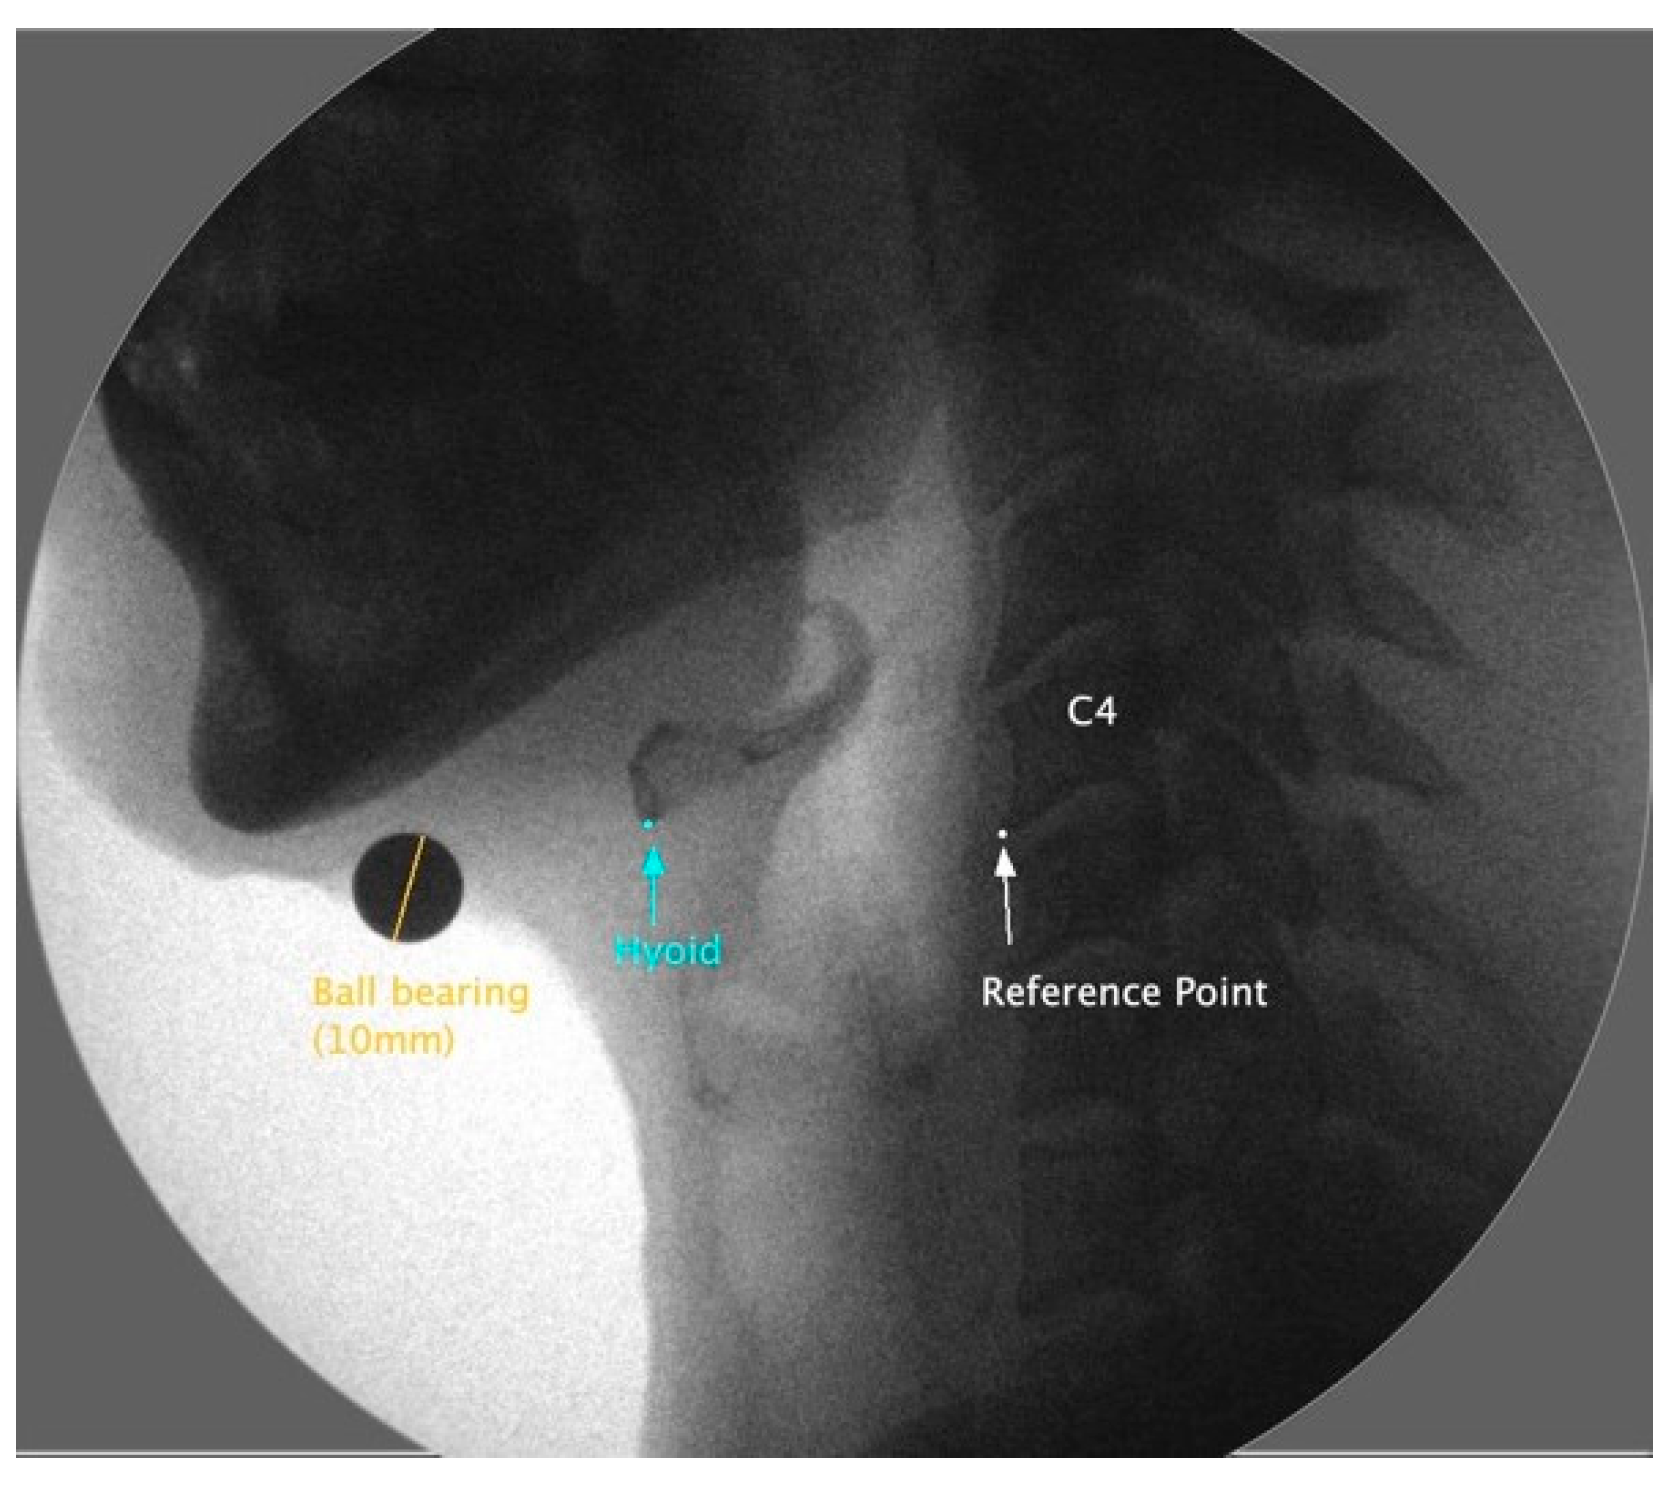

Frame-by-frame analysis determined the resting and maximum displacement positions of the hyoid bone. Still images were generated from the videos to capture these two positions for measurement. Using imaging software, ImageJ 1.53, the images were scaled using a ball bearing (10 mm) and analyzed to identify the coordinates of the most anterior and inferior point of C4 for a reference point and the most anterior and inferior corner of the hyoid bone, as seen in Figure 2.

Figure 2.

This is a lateral view of a videofluoroscopic frame of the resting hyoid bone (blue), showing the C4 frame reference point (white). The orange line illustrates the ball bearing length to which the measurements are scaled.